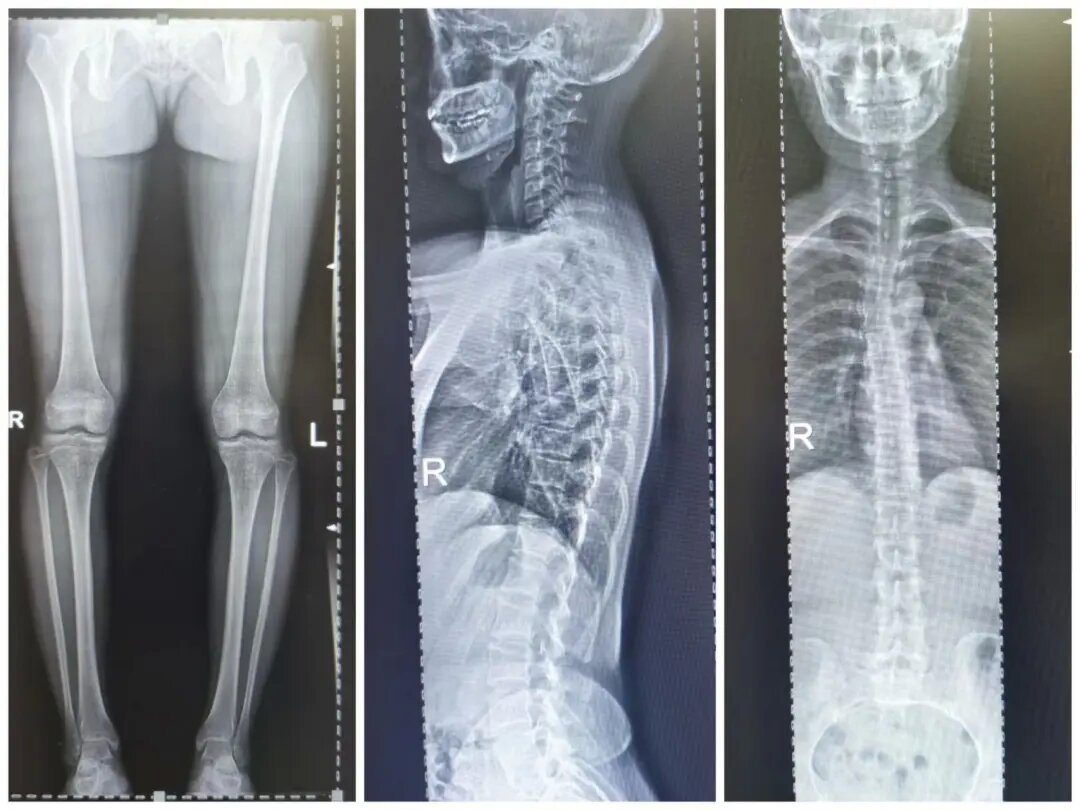

四、脊柱全长摄影及双下肢全长摄影

对脊柱侧弯、髋关节置换、膝关节置换给予全面、直观的影像资料。

数字胃肠透视机全脊柱摄影